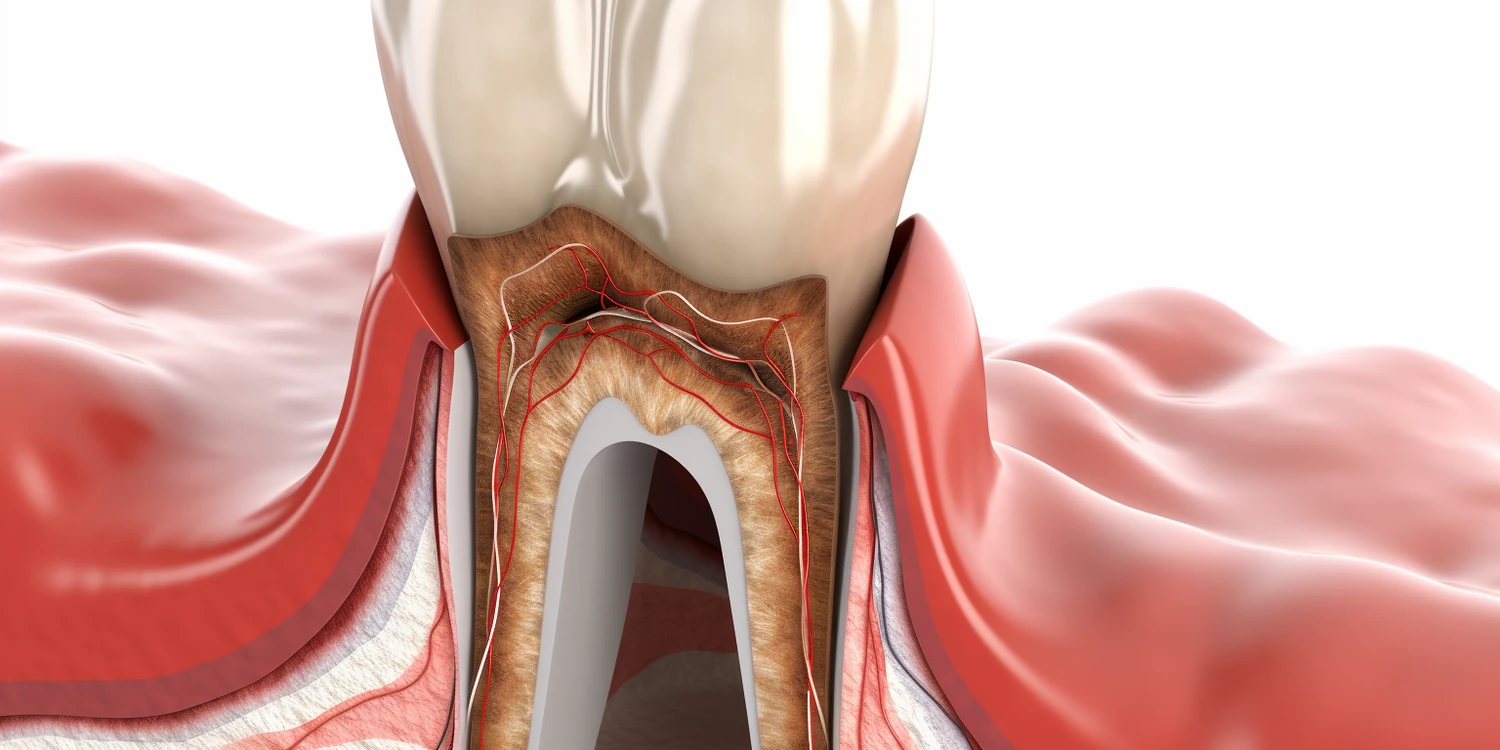

Protetyka na implantach w Lublinie to dziedzina stomatologii, która zajmuje się odbudową zębów przy użyciu implantów dentystycznych. Implanty są sztucznymi korzeniami zębów, które są wszczepiane w kość szczęki lub żuchwy, a następnie pokrywane koronami, mostami lub protezami. Dzięki tej metodzie pacjenci mogą cieszyć się pełnym uzębieniem, co wpływa na ich komfort życia oraz estetykę uśmiechu. W Lublinie wiele klinik oferuje usługi związane z protetyką na implantach, co sprawia, że pacjenci mają dostęp do nowoczesnych technologii i wykwalifikowanego personelu. Proces leczenia zaczyna się od szczegółowej diagnostyki, w tym zdjęć rentgenowskich oraz tomografii komputerowej, które pozwalają ocenić stan kości i zaplanować zabieg. Następnie lekarz wykonuje zabieg wszczepienia implantu, który po kilku miesiącach integruje się z kością.

Proces leczenia w protetyce na implantach w Lublinie składa się z kilku kluczowych etapów, które zapewniają skuteczność oraz bezpieczeństwo całej procedury. Pierwszym krokiem jest konsultacja stomatologiczna, podczas której lekarz ocenia stan uzębienia pacjenta oraz wykonuje niezbędne badania diagnostyczne. Na podstawie uzyskanych wyników lekarz może zaplanować dalsze działania oraz omówić z pacjentem wszystkie dostępne opcje leczenia. Po zaakceptowaniu planu leczenia następuje etap wszczepienia implantu. Zabieg ten przeprowadzany jest w znieczuleniu miejscowym i zazwyczaj trwa od jednej do dwóch godzin. Po wszczepieniu implantu konieczne jest odczekanie kilku miesięcy na jego integrację z kością. W tym czasie pacjent może korzystać z tymczasowych rozwiązań protetycznych. Gdy proces gojenia się zakończy, lekarz przystępuje do wykonania odbudowy protetycznej, czyli zakupu korony lub mostu na implancie.

Rehabilitacja po zabiegu protetyki na implantach w Lublinie to proces, który może trwać różnie w zależności od indywidualnych warunków zdrowotnych pacjenta oraz rodzaju zastosowanej procedury chirurgicznej. Po wszczepieniu implantu następuje okres gojenia trwający zazwyczaj od trzech do sześciu miesięcy, podczas którego implant integruje się z kością szczęki lub żuchwy. W tym czasie pacjent może otrzymać tymczasowe rozwiązania protetyczne umożliwiające normalne funkcjonowanie i estetyczny wygląd uśmiechu. Po zakończeniu procesu gojenia lekarz przystępuje do wykonania stałej odbudowy protetycznej, co również wymaga czasu na precyzyjne dopasowanie koron lub mostów do pozostałych zębów pacjenta.